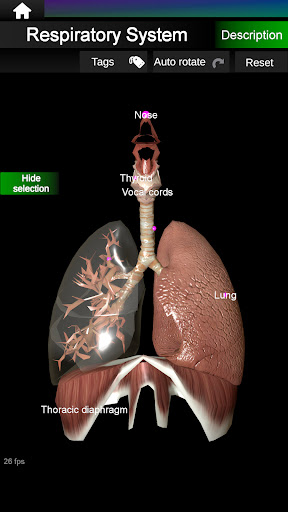

Menampilkan model anatomi 3D dari organ utama tubuh manusia dan penjelasannya masing-masing.

Apa yang ada di aplikasi?

* Sistem pernafasan, yang meliputi trakea, bronkus, paru-paru dan animasi sistem ini.

* Mudah diakses dan dinavigasi (zoom, rotasi 3D).

* Sembunyikan atau tampilkan informasi.

* Deskripsi masing-masing organ.